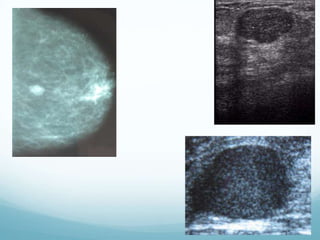

 Mamografía: patrón nodular bilateral de diferentes tamaños

 Ecografía: nódulos anecóicos, bien limitados, pared fina y refuerzo acústico

posterior, puede servir como guía para aspiración del quiste

• Por USG: Definida, hipoecóica